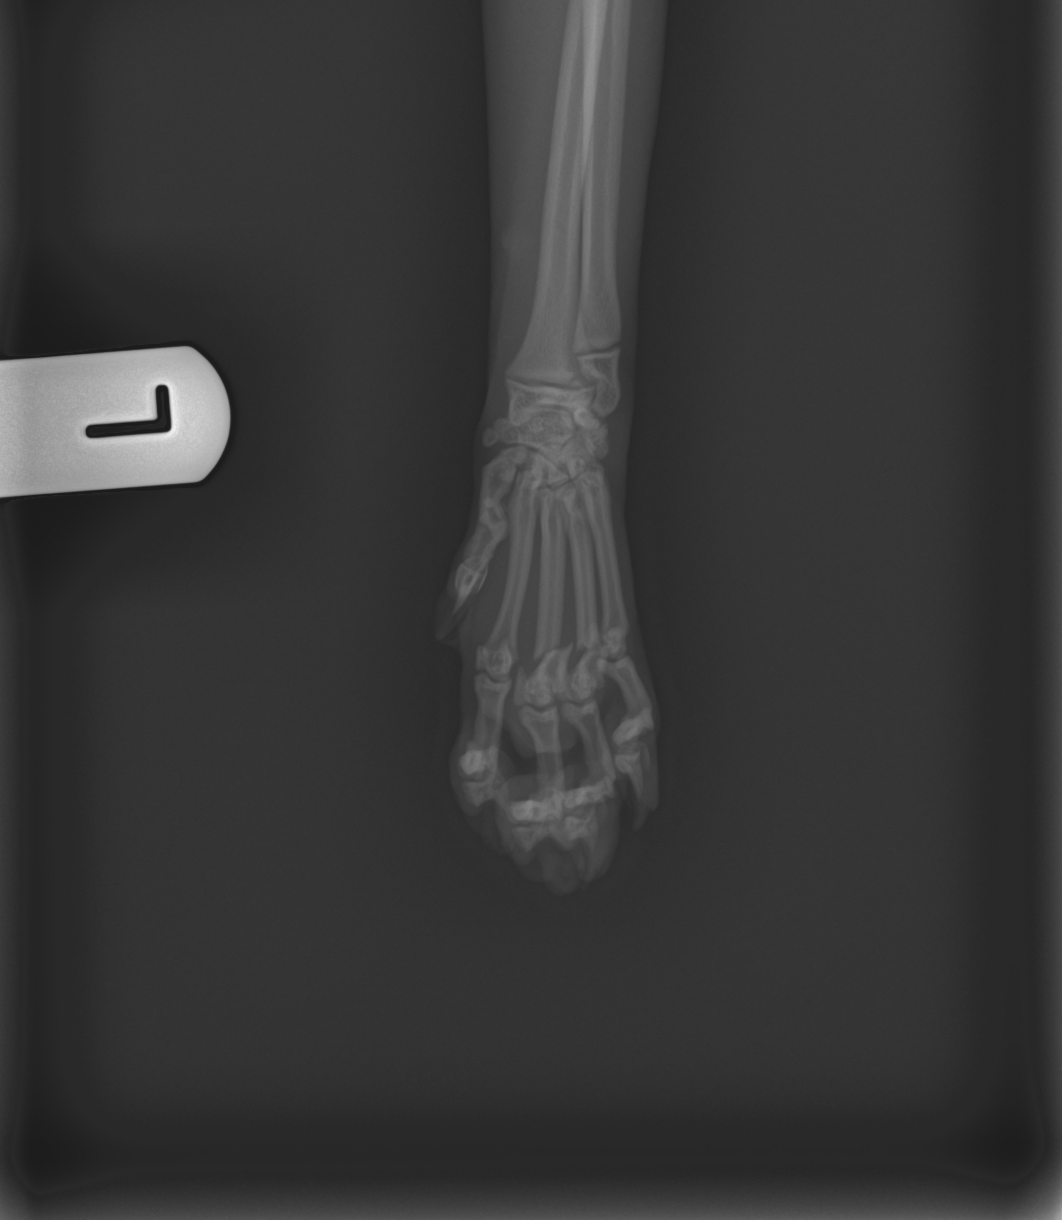

Levamo-lo de imediato ao veterinário, onde foi feita uma ecografia abdominal que, felizmente, não mostrou alterações internas. No entanto, o raio-x revelou fraturas, no rádio da pata dianteira direita e no metacarpo da pata dianteira esquerda.